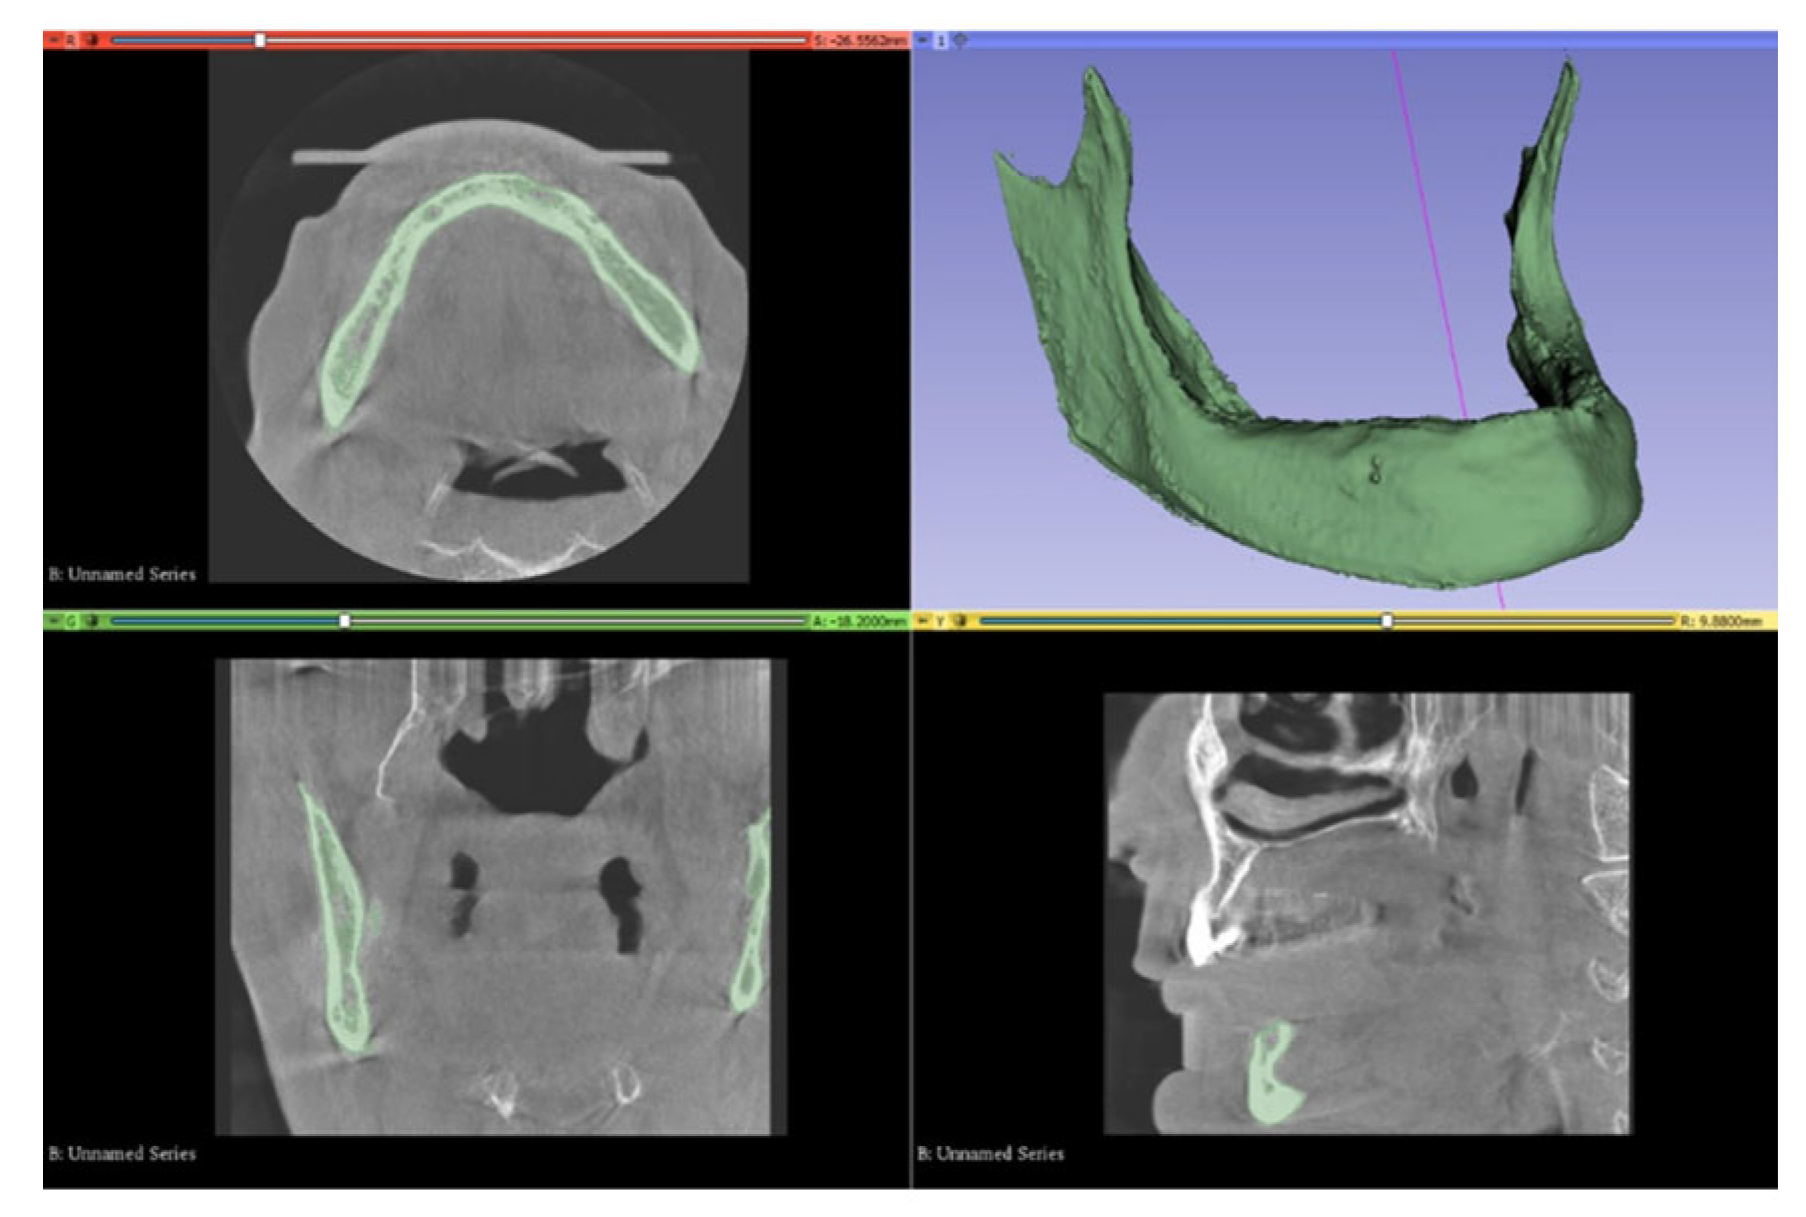

2.1. Modeling of Cortical Bone, Trabecular Bone, and Teeth

2.2. Modeling of Implants, Abutments, Screws, Mandibular Canal, and Graft: Creation of Study Models